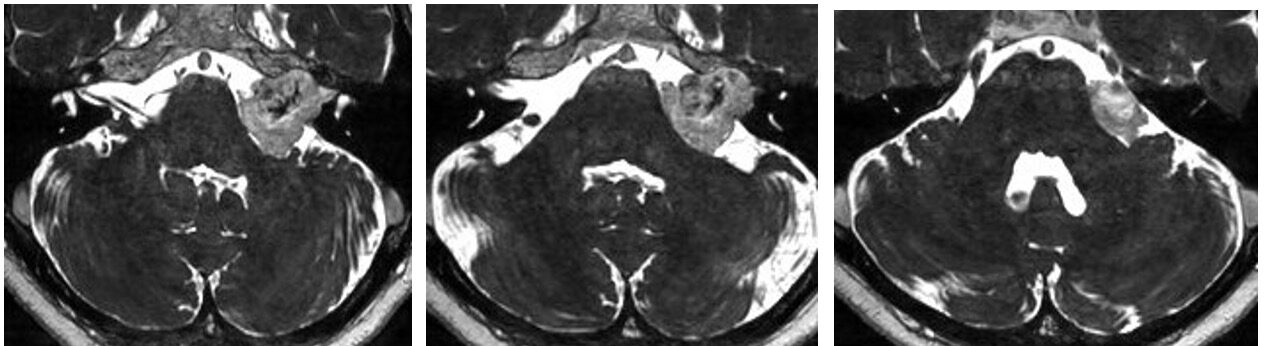

今回は内耳道底部まで完全に開放でき、顔面神経起始部を含め、腫瘍はLast 10mmの部分以外はほぼ完全に摘出できました。しかしLast 10mmを剥離していたところやはり顔面神経モニターが0.1mAでは反応しなくなり、0.2-0.5mAでは反応があるところで摘出を終了しました。術後HB grade 5の顔面麻痺が出現しましたが、耳鼻科のENGの反応はよく術後2ヶ月で回復しました。